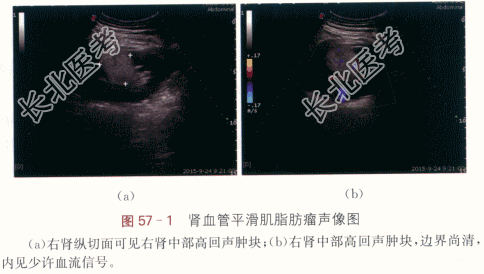

患者,女性,51岁,因“体检发现右肾占位2周”就诊。否认血尿、尿频、尿急、尿痛、腹痛及头晕等不适。

二、影像资料